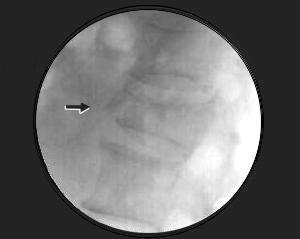

Corte sagital

Flecha: Observe la fractura del cuerpo vertebral L1, con escaso compromiso del canal medular.